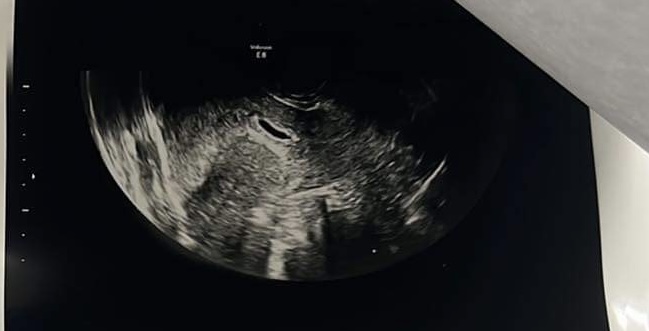

Badanie usg, za mały pęcherzyk

W dniu dzisiejszym byłam na potwierdzeniu ciąży Pan doktor powiedział ze jest zle. Pęcherzyk jest za mały i ma zły kształt. Wymiar to 11mm.

Bardzo was proszę o pomoc, co o tym myślicie? Była któraś z was w takiej sytuacji? Czy na tym zdj jest pęcherzyk żółtkowy? Nie wiem co mam o tym myśleć. Proszę o odpowiedz.